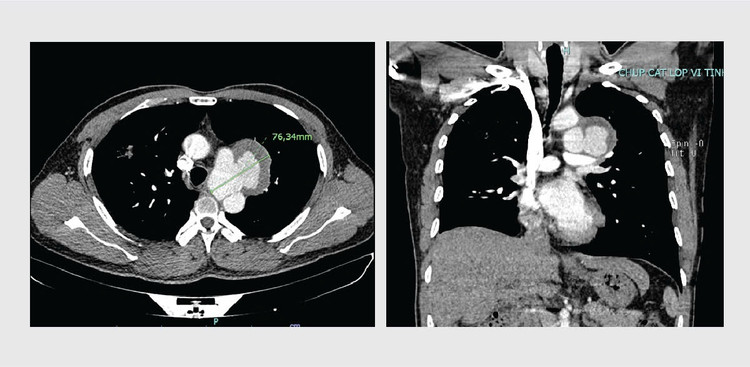

| Hình ảnh khối phình động mạch chủ ngực của người bệnh trên phim chụp CT - ảnh BVCC |

Với kích thước khối phình lớn ~ 7cm, nếu không chủ động được can thiệp sớm người bệnh phải đối diện với nguy cơ vỡ khối phình, gây mất máu cấp trầm trọng, thậm chí dẫn đến tử vong bất kỳ khi nào.